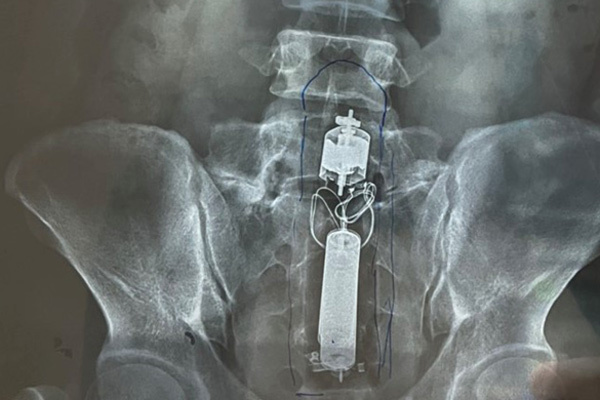

Nam thanh niên mắc kẹt dương vật giả trong hậu môn

Qua kết quả chụp X-quang, bác sĩ phát hiện dị vật mắc kẹt trong trực tràng nam thanh niên 31 tuổi, ngụ TP.HCM.